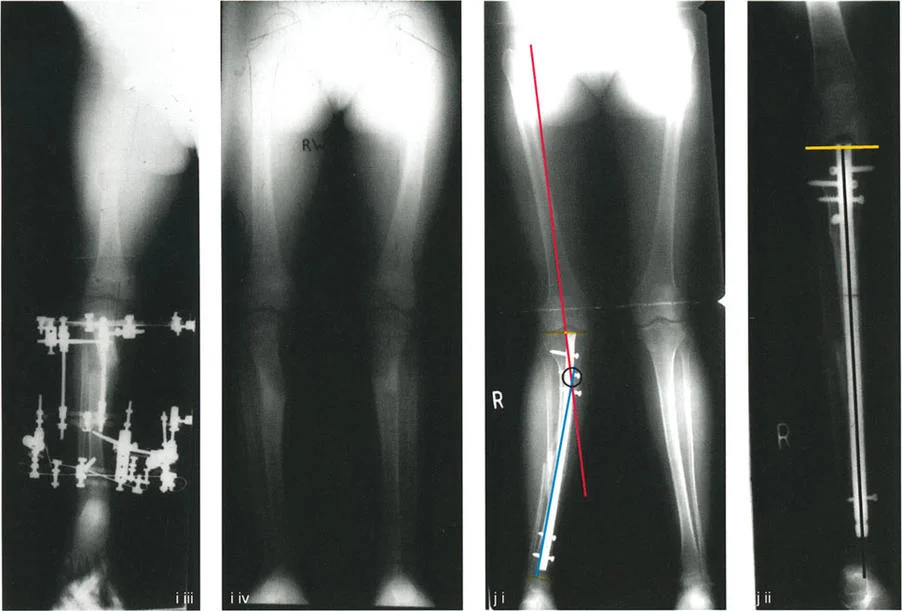

التصوير بالأشعة السينية (X-rays):

- أشعة الساق الكاملة الواقفة (Full-length Standing X-rays): هذه هي الأداة التشخيصية الأكثر أهمية لتشوهات الأطراف. يتم أخذ الصورة بينما يقف المريض، مما يسمح بتقييم المحور الميكانيكي للطرف بأكمله (من الورك إلى الكاحل) تحت تأثير تحمل الوزن. تتيح هذه الصور للجراح قياس زوايا محددة بدقة وتحديد "مركز دوران التشوه" (CORA) – وهو النقطة المحورية التي يجب أن يتم التصحيح حولها.

أهمية التخطيط الدقيق لقطع العظم

إن نجاح جراحة تصحيح تشوهات الأطراف يعتمد بشكل كبير على التخطيط المسبق الدقيق. هذا التخطيط أشبه برسم خارطة طريق هندسية تضمن أن كل خطوة جراحية تقود إلى النتيجة المرجوة. يعتمد هذا التخطيط على "مبادئ بالي" التي تحدد ثلاثة متغيرات هندسية أساسية في كل حالة:

- مركز دوران التشوه (CORA - Center of Rotation of Angulation): هذه هي النقطة المحورية للتشوه في العظم. يحددها الجراح من خلال رسم محاور الطرف قبل الجراحة.

- محور تصحيح الزاوية (ACA - Angulation Correction Axis): هذه هي النقطة التي يدور حولها الجزء البعيد من العظم لتصحيح التشوه. يتحكم الجراح في هذه النقطة عن طريق وضع المفصلات على المثبت الخارجي أو نقطة الارتكاز للوحة التثبيت.

- مستوى قطع العظم (Osteotomy Level): هذا هو الموقع الفعلي الذي يتم فيه قطع العظم. يتحكم الجراح بشكل كامل في هذا المتغير، ويتم اختياره بناءً على عوامل مثل الأنسجة الرخوة، وجودة العظم، ونوع الأجهزة المستخدمة.

النتيجة النهائية للتصحيح تعتمد كليًا على كيفية ارتباط هذه المتغيرات الثلاثة ببعضها البعض. الفشل في التخطيط الدقيق يمكن أن يؤدي إلى "تشوهات ثانوية" غير مرغوب فيها، مثل انحراف المحور الميكانيكي أو ترجمة (إزاحة) العظم.